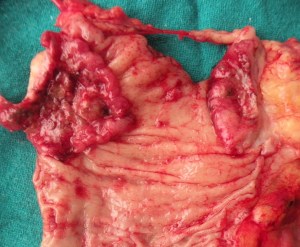

a A mesenteric cyst (diagnosed clinically and on CT) turned out to be big ovarian cyst. easily removed at laparotomy.

A rectal cancer (low) resected and a stapled anastomosis low in the rectum performed.